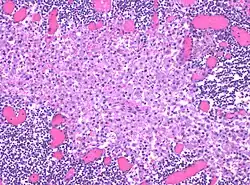

Sinus histiocytosis, a common feature in lymph node biopsies, is characterized by dilated sinuses containing variable numbers of histiocytes.[4]